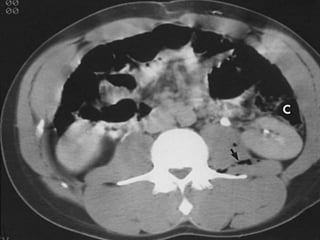

Computed tomography

Imaging study of choice for hemodynamically stable

patient

Sensitive and specific

Advantages

(1) Functional and anatomic assessment of the kidneys

and urinary tract

(2) Establish the presence or absence of 2 functional

kidneys

(3) Diagnosis of concurrent injuries

(4) Delineates extravasations, segmental infarcts, and

hematoma

Disadvantages

(1) Requires intravenous contrast

(2) Patient must be stable enough

(3) Full urinary assessment is dependent on the timing

of contrast and scanning in order to view the bladder

and ureters.